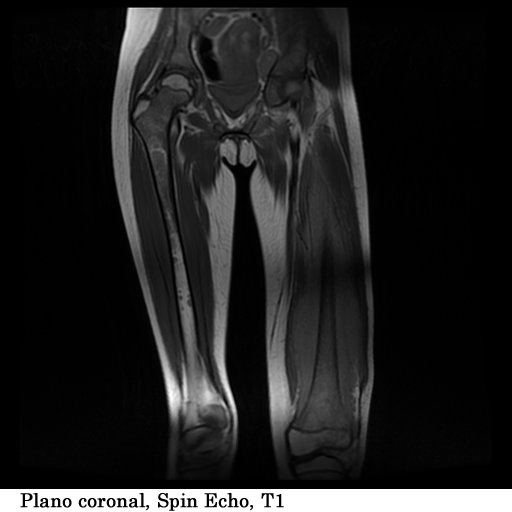

Paciente femenina, de 18 años de edad, con masa visible y palpable a nivel del tercio medio e inferior del fémur izquierdo, con un tiempo de evolución de 1 año, refiere dolor y limitación al movimiento.

TECNICA EMPLEADA

Se coloco al paciente en decúbito supino, utilizando una bobina fase array, haciendo adquisiciones en los planos axial, sagital y coronal, secuencias, spin echo, eco de gradiente e hibridas, potenciadas a T1, T2 y DP, secuencias Steer, y se obtuvieron imágenes con saturación de grasa.

HALLAZGOS IMAGENOLOGICOS

1. Edema de tejidos blandos que infiltra los músculos del muslo en su tercio medio y distal

2. Fractura patológica de tercio proximal de la diáfisis femoral izquierda

3. Engrosamiento del periostio del tercio medio y distal de la diáfisis femoral izquierda